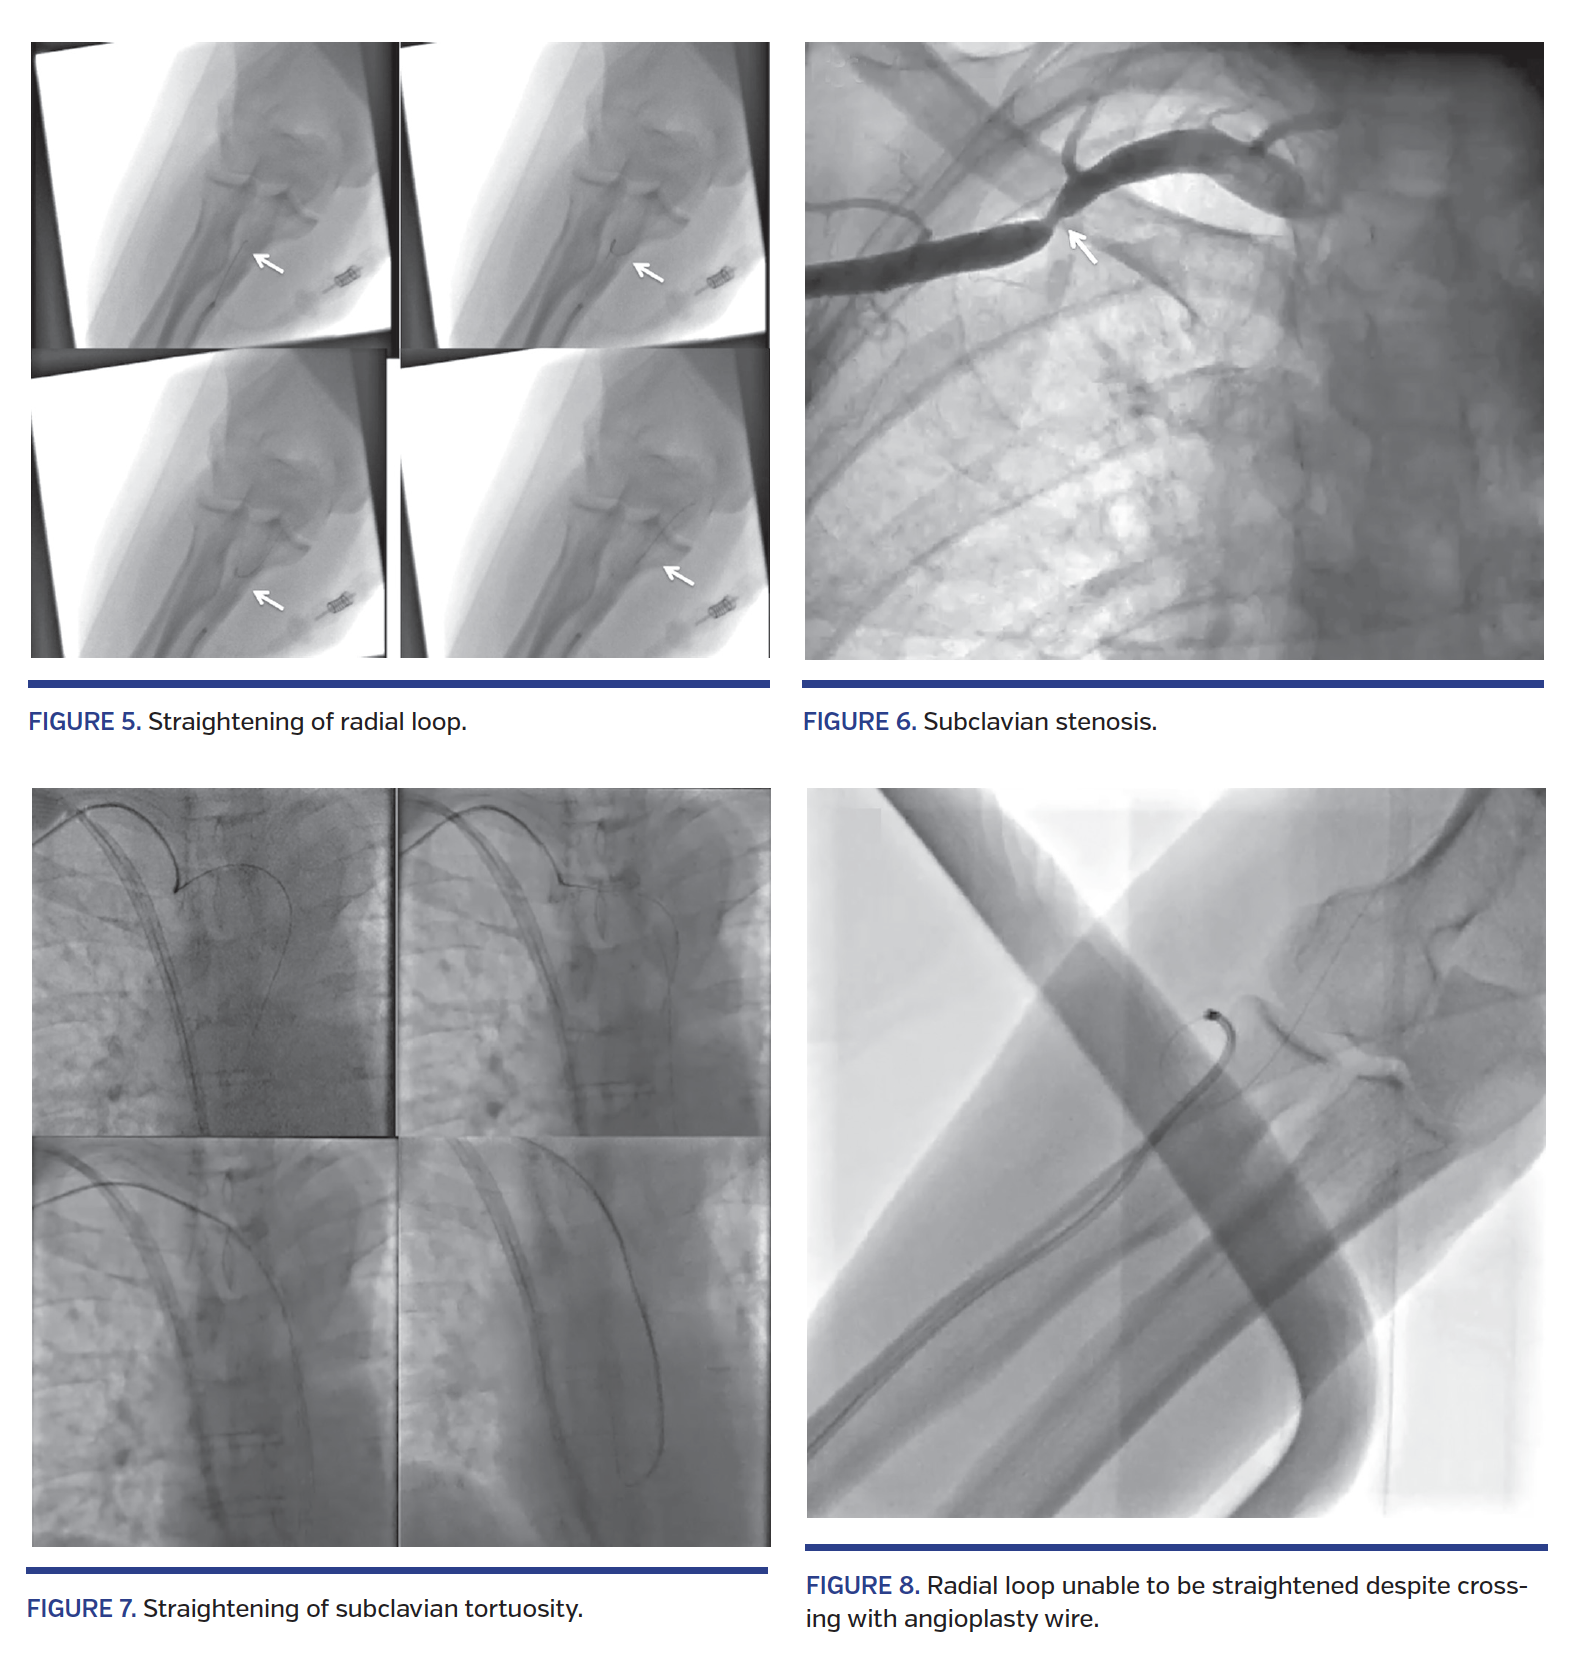

Success rates with individual obstacles/anomalies are provided in Table 4. Most of the obstacles/anomalies were successfully negotiated; however, extreme radial tortuosity and radial loops had relatively lower success rates (18% and 20%, respectively). Some of the radial loop and extreme radial tortuosity cases were negotiated successfully with the use of 0.35˝ hydrophilic wires or 0.014˝ angioplasty wires (Figure 5). Subclavian tortuosity and stenosis accounted for 58 cases (2.3%) (Figures 2 and 6). Of these, 73% were successively negotiated with the use of hydrophilic wires and/or breath-holding maneuvers, which helped in straightening the loop (Figure 7). Two of the subclavian tortuosity cases were arteria lusoria (retroesophageal course of the subclavian artery); in both cases, we failed to negotiate and had to switch to femoral access.

Most of the obstacles were at the radial and subclavian levels. Radial spasm and minor radial tortuosity were negotiated in most cases with the use of vasodilators and/or hydrophilic wires. Although some of the radial loops and extreme radial tortuosities were successfully negotiated, these anomalies had relatively higher failure rates. Previous studies evaluating such radial anomalies have also shown higher failure rates in radial loops and extreme radial tortuosities.19-23 In the learning-curve phase of the transradial approach, encountering these complex anomalies should encourage operators to switch the access site in order to preserve confidence (and more importantly, to avoid arterial complications).